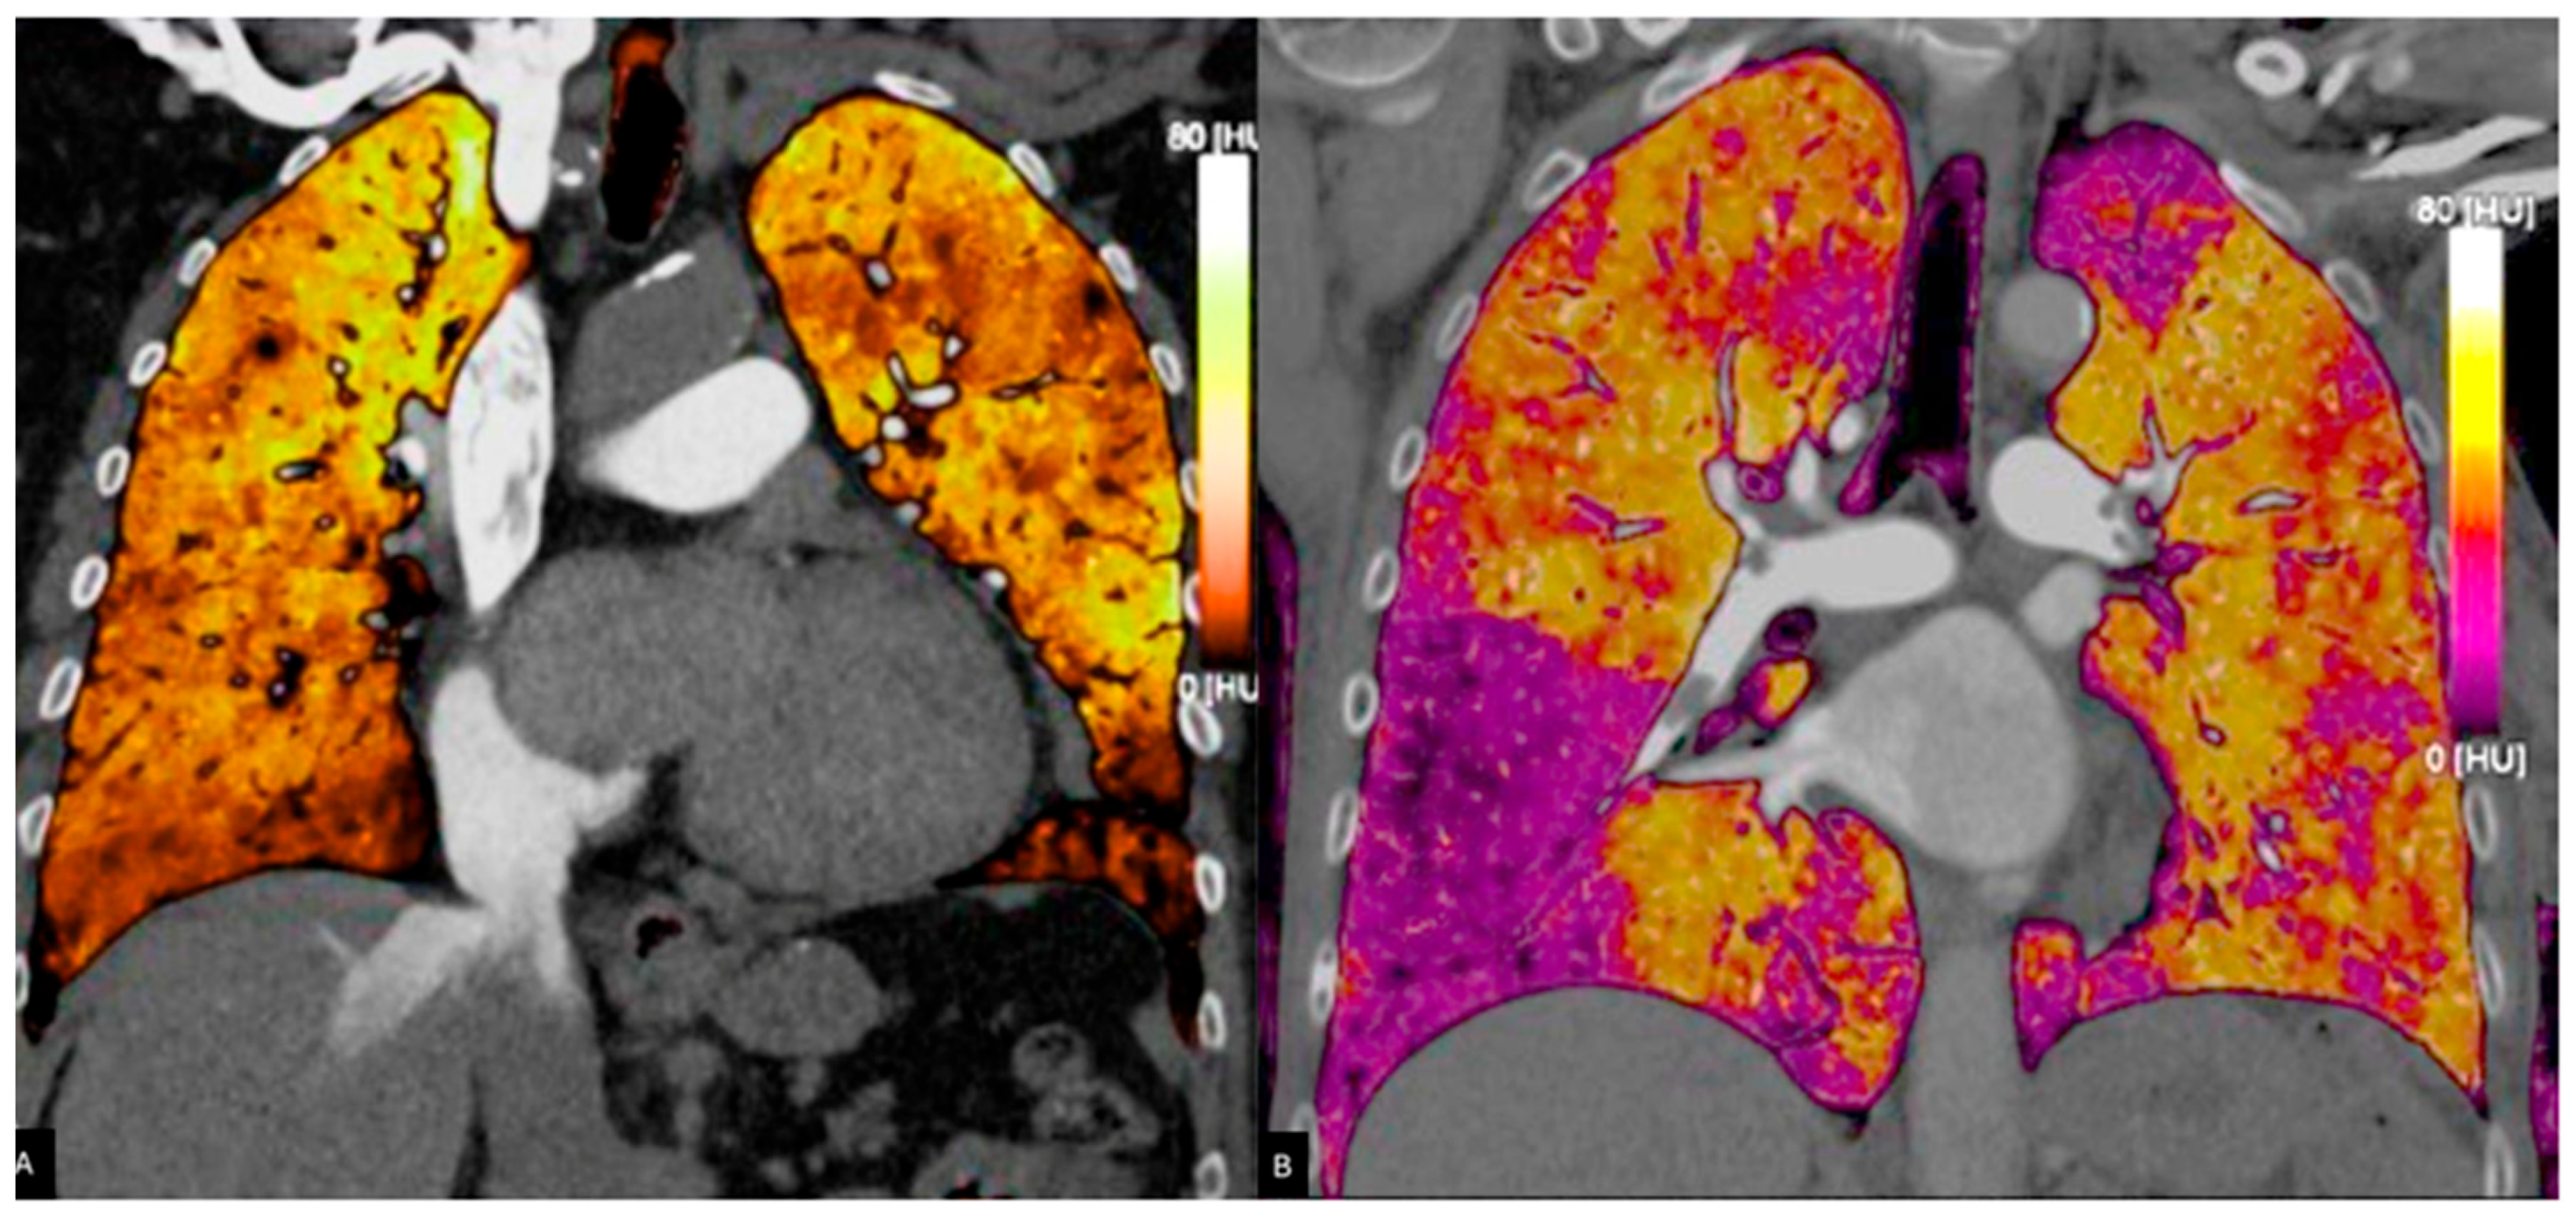

3.2. Dual Energy CT

3.2.1. Principles of DECT

3.2.2. Accuracy of DECT